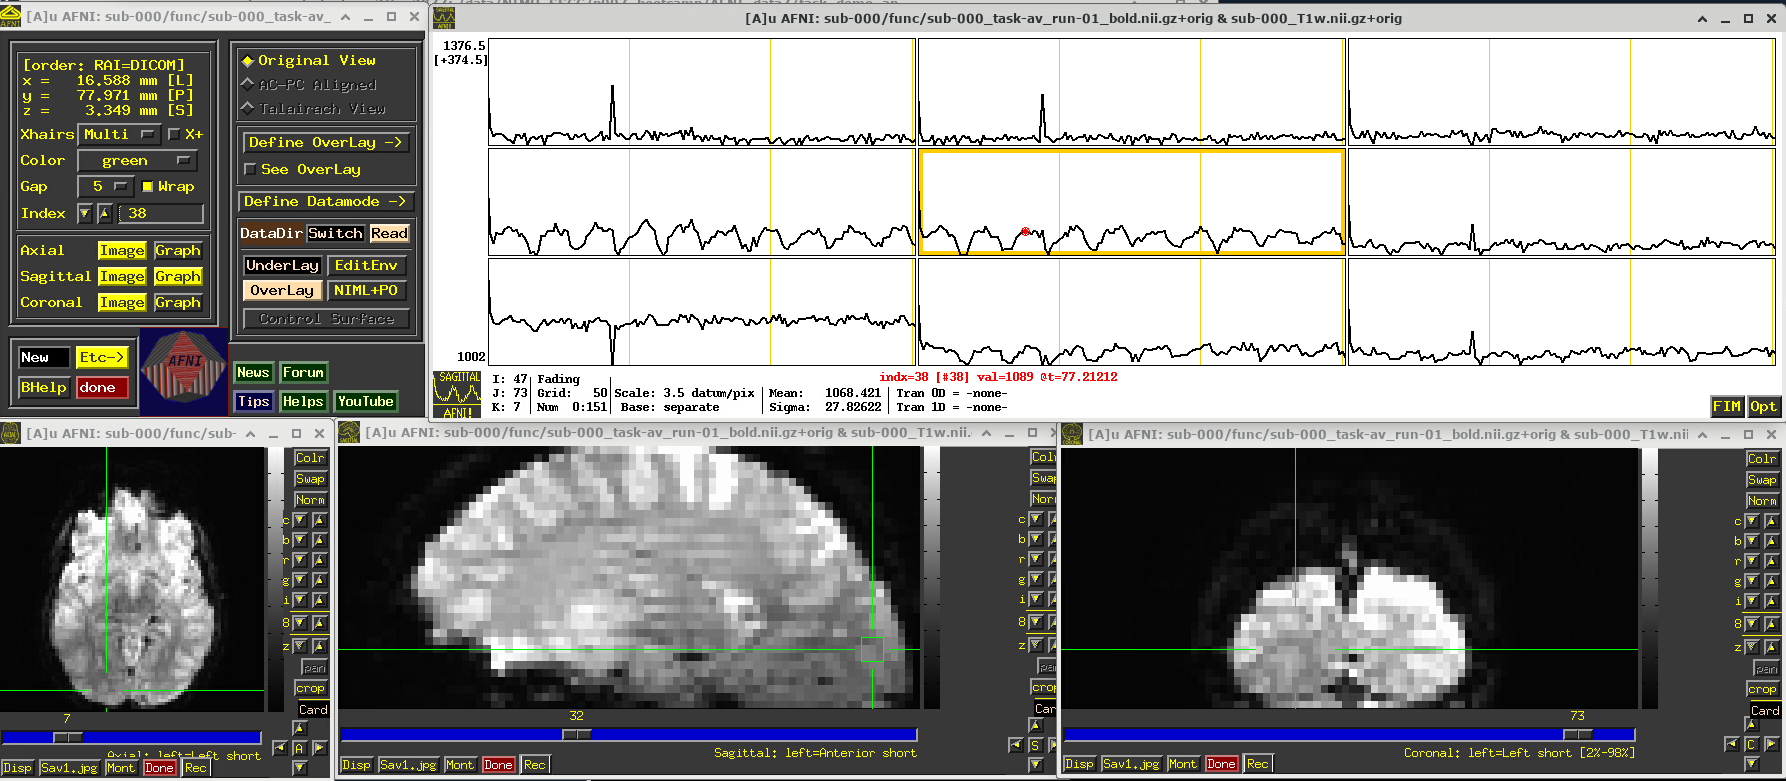

# Display a screenshot of the AFNI GUI with the first EPI run loaded, checking out spikes

IPython.display.Image(filename='example_snapshots/img_02_afnigui_epi_r01_spikes.png')

../../_images/46131ddfd698370db628152f22b5707ca1f78f9b0515788c32fe949500047e05.png

Click around and see how different parts of the brain appear. For example, if you end up at the location (x,y,z) ~ (8, 31, 60), you will see some spikes that are very big relative to the other fluctuations. These are due to a subject motion event about a quarter of the way through the run.

Some spikes are up, some are down, and some time series don’t appear to have any. This heterogeneity of motion-induced spikiness is one major reason why participant motion is so hard to navigate well in processing and analysis.

Up above, and here as well, you might also notice a subtle thing that appears in all time series at their very start—a different kind of spike. (It is hiding a bit, because of the y-axis there, but look closely.) This one is different because it is always upwards, uniformly. This has a different root cause. Each dataset looks normal there as a 3D volume, but in fact the recorded values are uniformly higher in the first few volumes than the rest—this is a “pre-steady state” phenomenon. It occurs generally in FMRI as the acquisition sequence settles into a steady state. Some scanners or initial data-streams clip out these time points, while others don’t. It is good to be aware that these can occur.

You can tell afni_proc.py to remove the first few EPI volumes, if the input data does include such pre-steady state volumes. And afni_proc.py will automatically check and warn you if it appears that the user did not account for some pre-steady state volumes that appear to be present. (And we note that participant motion can occur in the first few volumes, so sometimes it is hard to tell which affect might be happening, or if both are.) In any case, you need to make sure that your task-based timing files stay synchronous with the EPI datasets as processed!